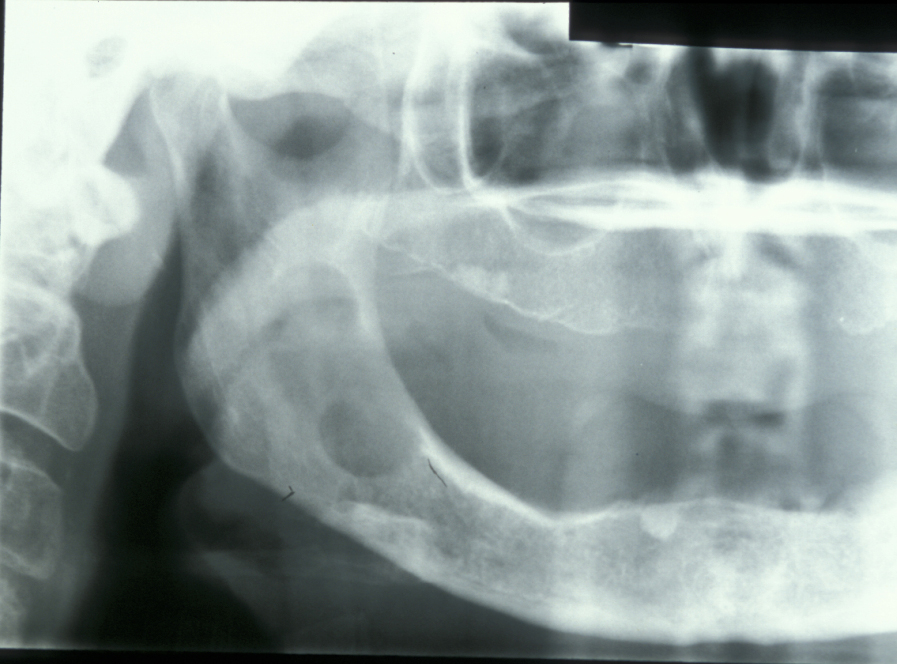

Limited resection represents a more aggressive form of removal of a cyst in that it will include the removal of bone in the vicinity of the cyst (a modified enucleation). It may also be a rim resection of the mandible (where a considerable portion of the mandibular bone is removed but a thin rim of the mandible is preserved to provide continuity of the bone). Treatment with Carnoy’s solution (a mixture of 60% alcohol, 30% chloroform and 10% concentrated acetic acid; applied locally directly after enucleation of a keratocyst) is popular with some surgeons. This is a way to reduce recurrence of keratocysts: the epithelial lining in keratocysts is very friable and therefore difficult to remove completely. Cryotherapy (local use of low temperature) may also have a role. A resection procedure with a reinforcing reconstruction plate is illustrated in Figures 10 to 15.

Figure 10: A large keratocyst, requiring more radical excision.

Figure 11: Approach to a large recurrent keratocyst that has grossly distorted the buccal cortex (outward facing cover of mandibular bone).